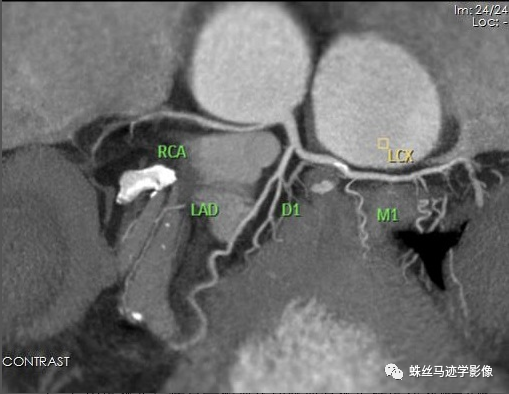

冠状动脉CTCA